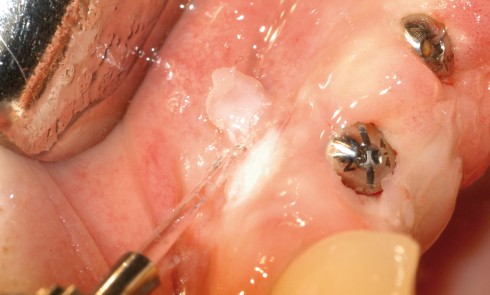

Article réservé à nos abonnés Le laser Er:YAG, un outil mini-invasif : applications cliniques en parodontie

Comme toutes les disciplines médicales et chirurgicales, la parodontie évolue et tend à devenir moins invasive. L’objectif est de proposer...